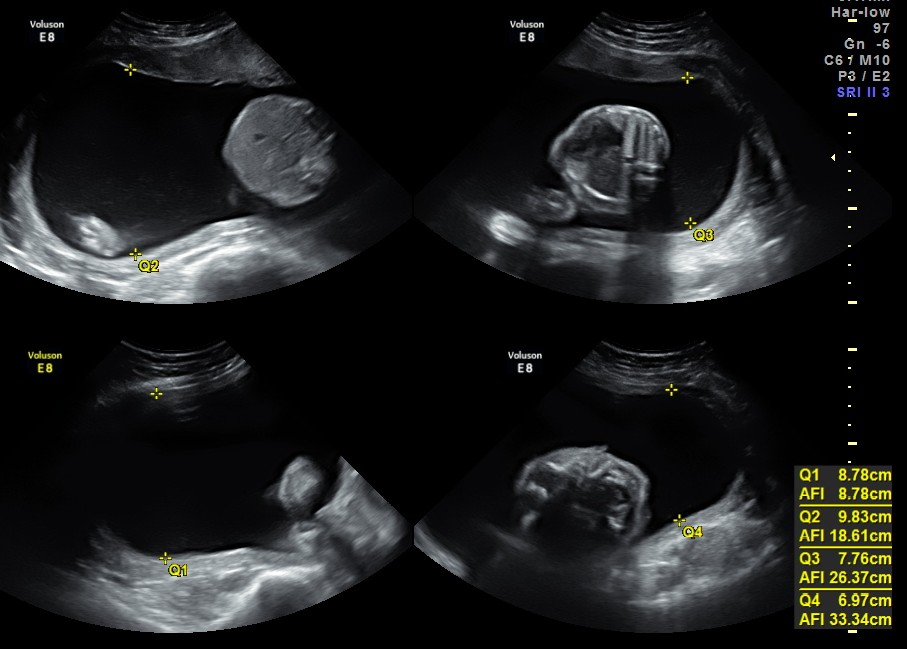

This was a 22 year old lady referred for evaluation of polyhydramnios.

She had severe polyhydramnios.